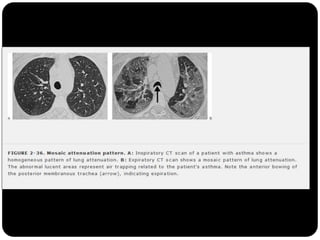

Perfusão em mosaico ( X vidro fosco)

O que foivisto até agora?  Cistos (LAM, Histiocistose de Langerhans, PIL)  Bolhas  Cavidades (diss. hemat. de infecção, neoplasia,TB, gran. Wegerner)  Enfisema (centrolobular)  Padrões e sinais torácicos Sinal deWestermark Sinal da corcova de Hampton Sinal de árvore em brotamento Perfusão em mosaico ( X vidro fosco) Faveolamento - fibrose